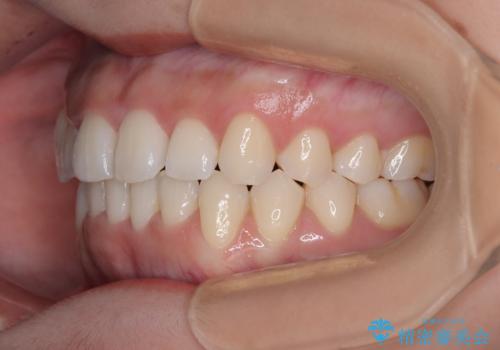

- 上下前歯のデコボコを気にして来院された患者様です。

上顎歯列が下顎の歯列に対して狭小であり、一部下顎の奥歯が上顎よりも外側に位置している状態でした。

上顎の急速拡大装置を使用して上顎骨を側方に拡大することで上顎歯列を拡大し、下顎歯列も拡大できるようにすることで、歯列を整えることとしました。